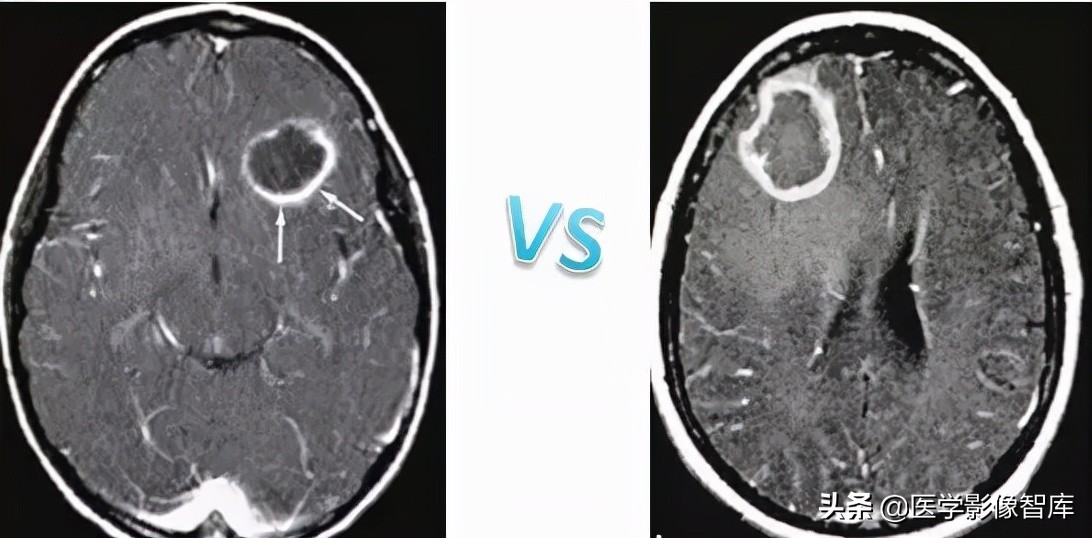

我先放两张环形强化的图,大家可以猜猜哪个是脑脓肿,哪个是脑肿瘤。

图4 环形强化病灶对比

DWI是鉴别脑脓肿与高级别胶质瘤、转移瘤等良好手段。对于上图两个病例,其实加做一个DWI序列的话,就很好区分。左图患者DWI明显高信号,ADC图低信号,是脑脓肿;右图患者DWI低信号,ADC图高信号,是脑肿瘤。

图5 环形强化对比(脑脓肿 vs 胶质母细胞瘤)